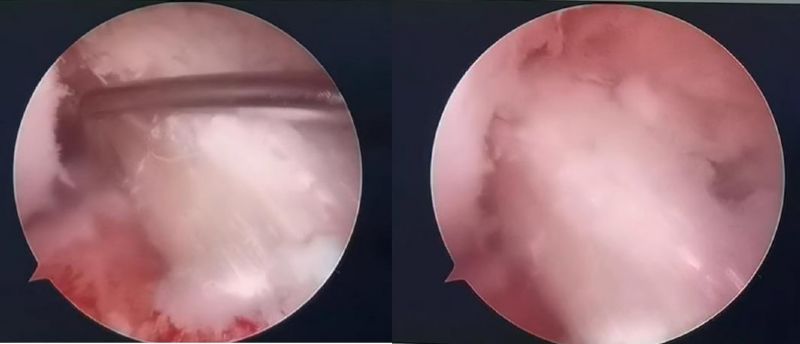

关节镜下软骨损伤

经患者同意后,李鹏主任手术团队制定详细手术方案。手术如期进行,经团队密切配合,对几位患者分别顺利完成关节镜下膝关节镜镜检、关节清理、股薄肌半腱肌取腱移植术、前交叉韧带重建术、软骨损伤微骨折术、半月板缝合修整术等。

镜下重建前交叉韧带走形、张力良好